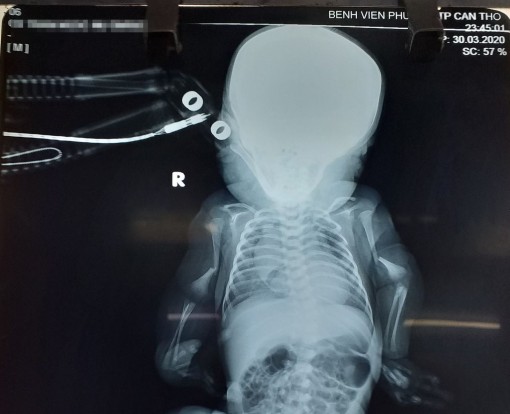

Các bác sĩ Khoa Nhi - Sơ sinh Bệnh viện Phụ sản TP Cần Thơ vừa phát hiện một trường hợp bé trai sơ sinh mắc bệnh xương thủy tinh, một bệnh lý bẩm sinh rất hiếm gặp, với tỉ lệ khoảng 1/10.000 trẻ.